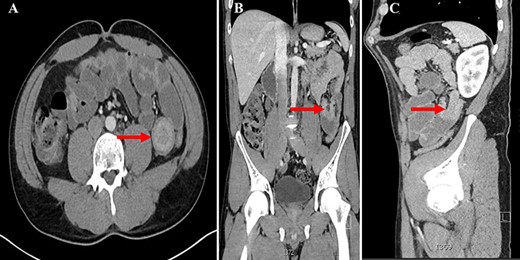

A. CT abdomen axial view showing the ‘Target Sign’ present within the small bowel; B. CT abdomen coronal view showing invagination of a proximal portion of small bowel into the adjacent section of bowel; C. CT abdomen sagittal view showing the aforementioned invagination of small bowel.

On exam, the patient was afebrile and tachycardic to 110 beats/minute. He appeared in acute distress but was oriented to person, place and time. His abdomen was non-distended but was rigid with severe abdominal pain with palpation in all four quadrants. Laboratory evaluation identified a leukocytosis to 16.5 K/mm3 with normal serum electrolytes and liver function tests. A CT was obtained, which showed a 4-cm segment entero-enteric intussusception without obstruction or signs of ischemia with non-specific bowel thickening proximal to the intussusception (Fig. 1). Given peritonitis on exam, the patient was taken to the operating room where the entero-enteric intussusception was identified and resected in bloc (Figs 2 and 3) No masses were palpated in the surgical specimen.